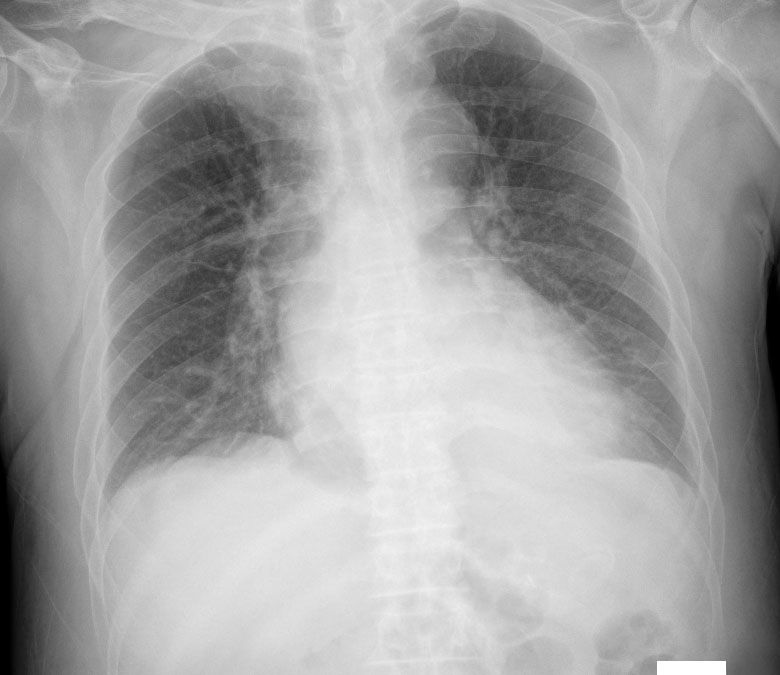

폐에 물 찬 정도가 다 빠진 게 맞나요?

저 상태는 괜찮은 상태가 맞을까요?

참고하시기 위해 다른 폐부종 사진을 첨부합니다. 한번의 사진으로 좋아졌다, 괜찮다를 판단하지 않고 이전 검사와 비교했을 때 좋아졌다, 괜찮다를 판단합니다. 그래서 한번의 x-ray가 괜찮냐 안 괜찮냐를 논하기 보다는 이전 검사와 비교해서 좋아졌는지 추세가 더 중요하다고 할 수 있습니다.

예전에 폐에 물이 찼을 때 사진은 제가 보지않았지만 현재로서는 폐에 물은 없어보이고 심비대소견만 보입니다.

폐부종이 있으셨다면 저 엑스레이사진은 많이 좋아졌다고 볼 수 있겠고, 심비대가 약간 의심스럽긴 하지만 고혈압을 오래 앓으셨다면 동반되는 변화이므로 심기능에 이상이 없을 경우 크게 문제삼지는 않을 것으로 보입니다.